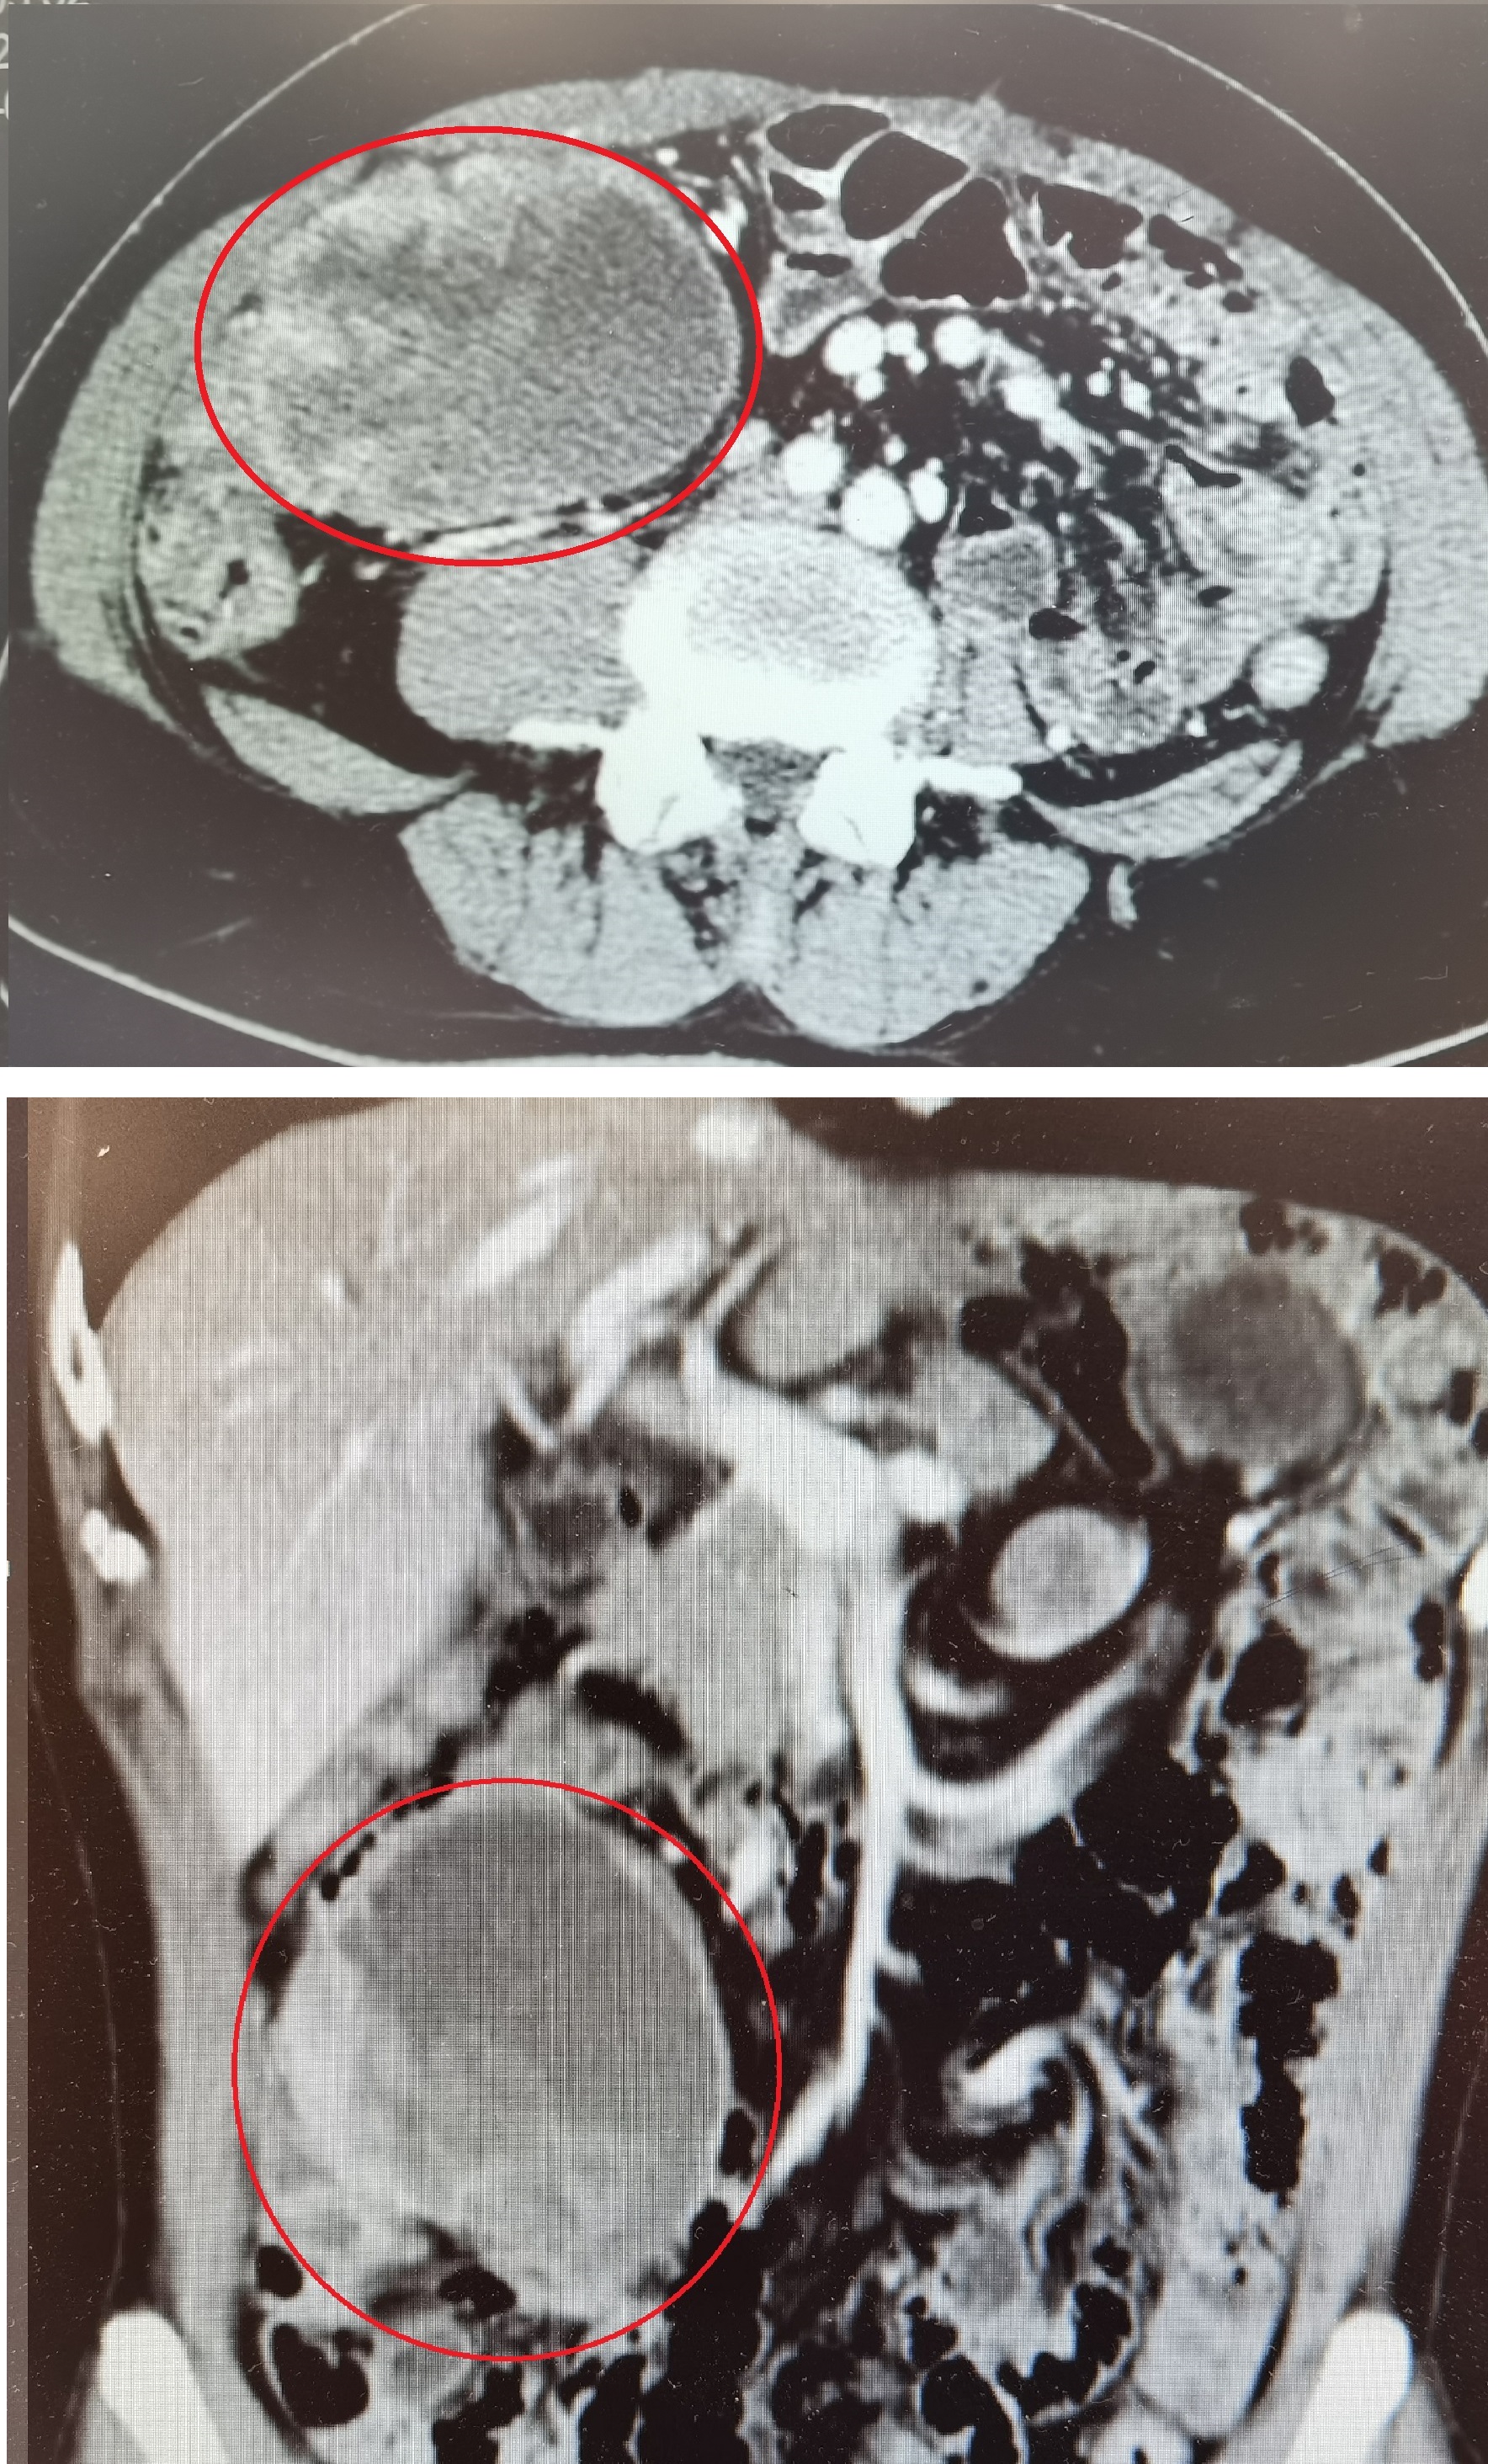

术后治疗:术后3年规律服用格列卫400mg/日治疗,至2018年复查胸腹部CT未见复发迹象。2019年10月(术后4年)查全腹CT发现腹腔多发肿块,较大者位于肝内下缘(约8.7×6.25×3.6cm),考虑转移,对比前片为新出现病灶。继续口服格列卫400mg/日。6个月后复查腹部CT提示肿瘤缩小,较大者位于肝内下缘(约3.5×3.2cm)。但口服格列卫12个月后(术后5年)复查腹部CT显示部分较前增大,较大者位于回盲部(约8.3×4.7cm)。进一步查PET/CT提示“胃间质瘤术后”改变,术区未见异常糖代谢增高灶;肝S6下缘结节及腹腔肿块(肝S6下缘及腹腔见软组织结节,大者直径约2.22cm)、盆腔肿块(盆腔见低密度肿块影,大小约8.8×6.5cm,边界欠清。),糖代谢增高,考虑转移。2020年12月底再次入院,自觉右下腹时有隐痛,未见恶心呕吐、排便困难等。住院期间请介入科会诊,行超声引导下腹腔肿块穿刺活检术,完善活组织分子病理检查:(腹腔肿物)梭形细胞肿瘤,结合临床病史和免疫组化结果,符合胃肠道间质瘤术后复发转移,伴片状坏死。

2019年复查CT提示肿瘤复发转移